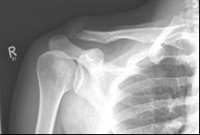

Picture 1 Picture 2

Picture 1: Displaced fracture of the left collarbone before surgery.